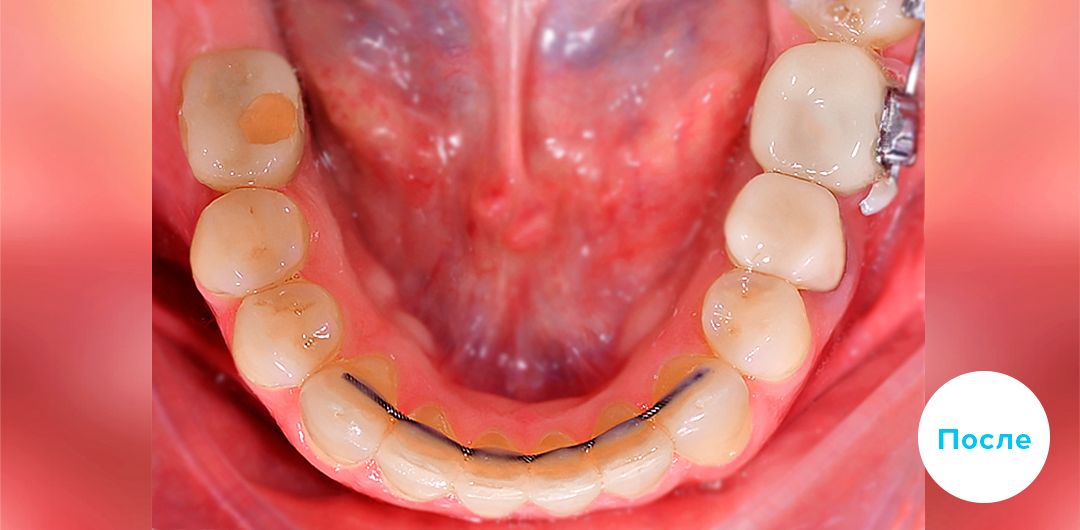

Результаты лечения